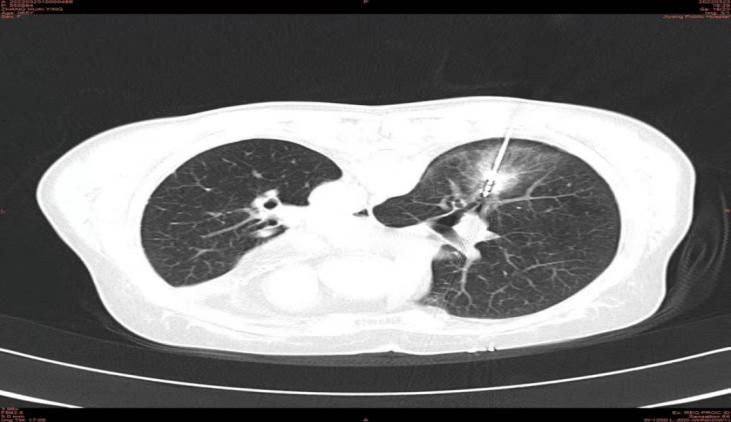

经过一段时间的恢复,3月22日,患者在家属的陪伴下来到我院介入微创科行右肺下叶病变的治疗;3月24日,在影像科及介入微创科团队协同操作下为患者实施了CT引导下经皮微波消融术,整个介入手术操作过程顺利,患者生命体征平稳,无明显不适及并发症发生,术后二十四小时复查胸部CT示微波消融范围理想,病灶位于消融靶心。

术后